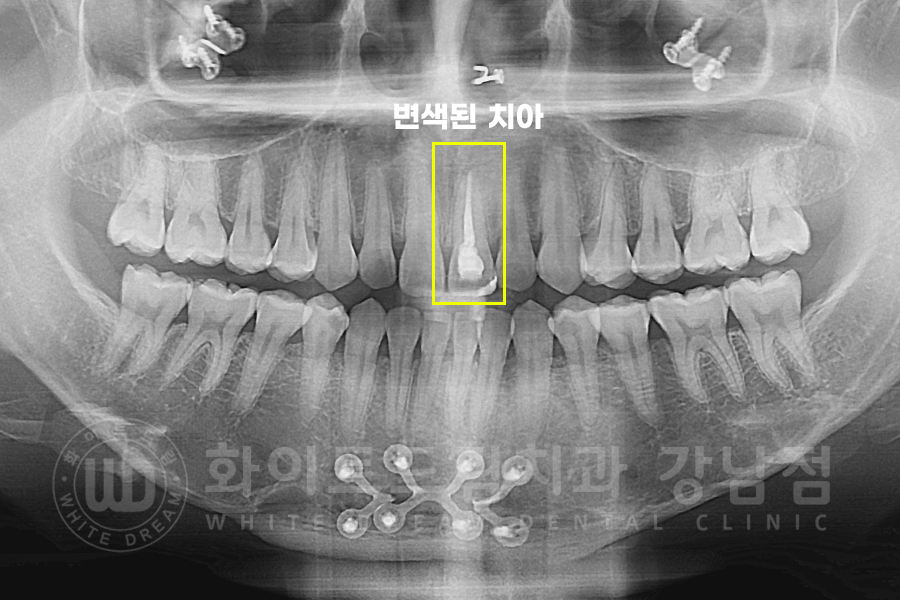

환자분의 x-ray 사진입니다.

기존 신경 치료 상태를 확인하는 과정인데요.

치근단 부위에 염증도 없고 특별히 불편한 증상은 없다고 하셔서 신경치료를 진행하지 않고 크라운 치료에 들어갔습니다.